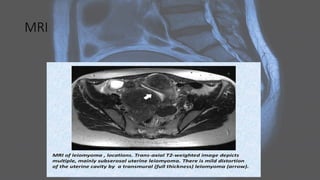

MRI

Uterine leiomyomas • Uterineleiomyomas, also known as uterine fibroids, are benign tumors of myometrial origin and are the most common solid benign uterine neoplasms. They are a common incidental finding on imaging and rarely cause diagnostic dilemma. Plain radiograph • Popcorn calcification within the pelvis may suggest the diagnosis.

CT • fibroids areusually seen as soft tissue density lesions and may exhibit coarse peripheral or central calcification • they may distort the usually smooth uterine contour • enhancement pattern is variable